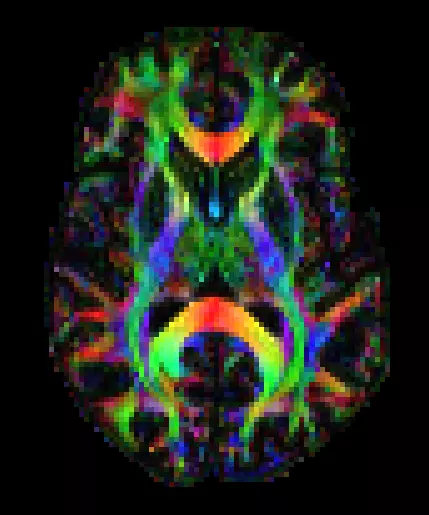

For the past ~6 years I have researched sports-related concussions at the Dettwiler Lab at the Princeton Neuroscience Institute. We use a special type of MRI called diffusion tensor imaging (DTI) to track the recovery process and look at the long term effects of concussion on the white matter of the brain.